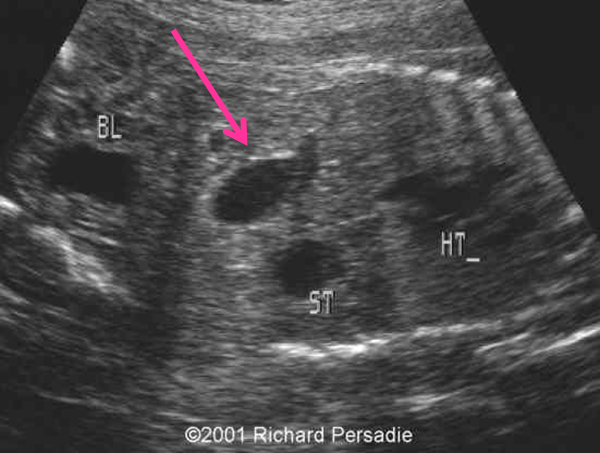

duodenal atresia